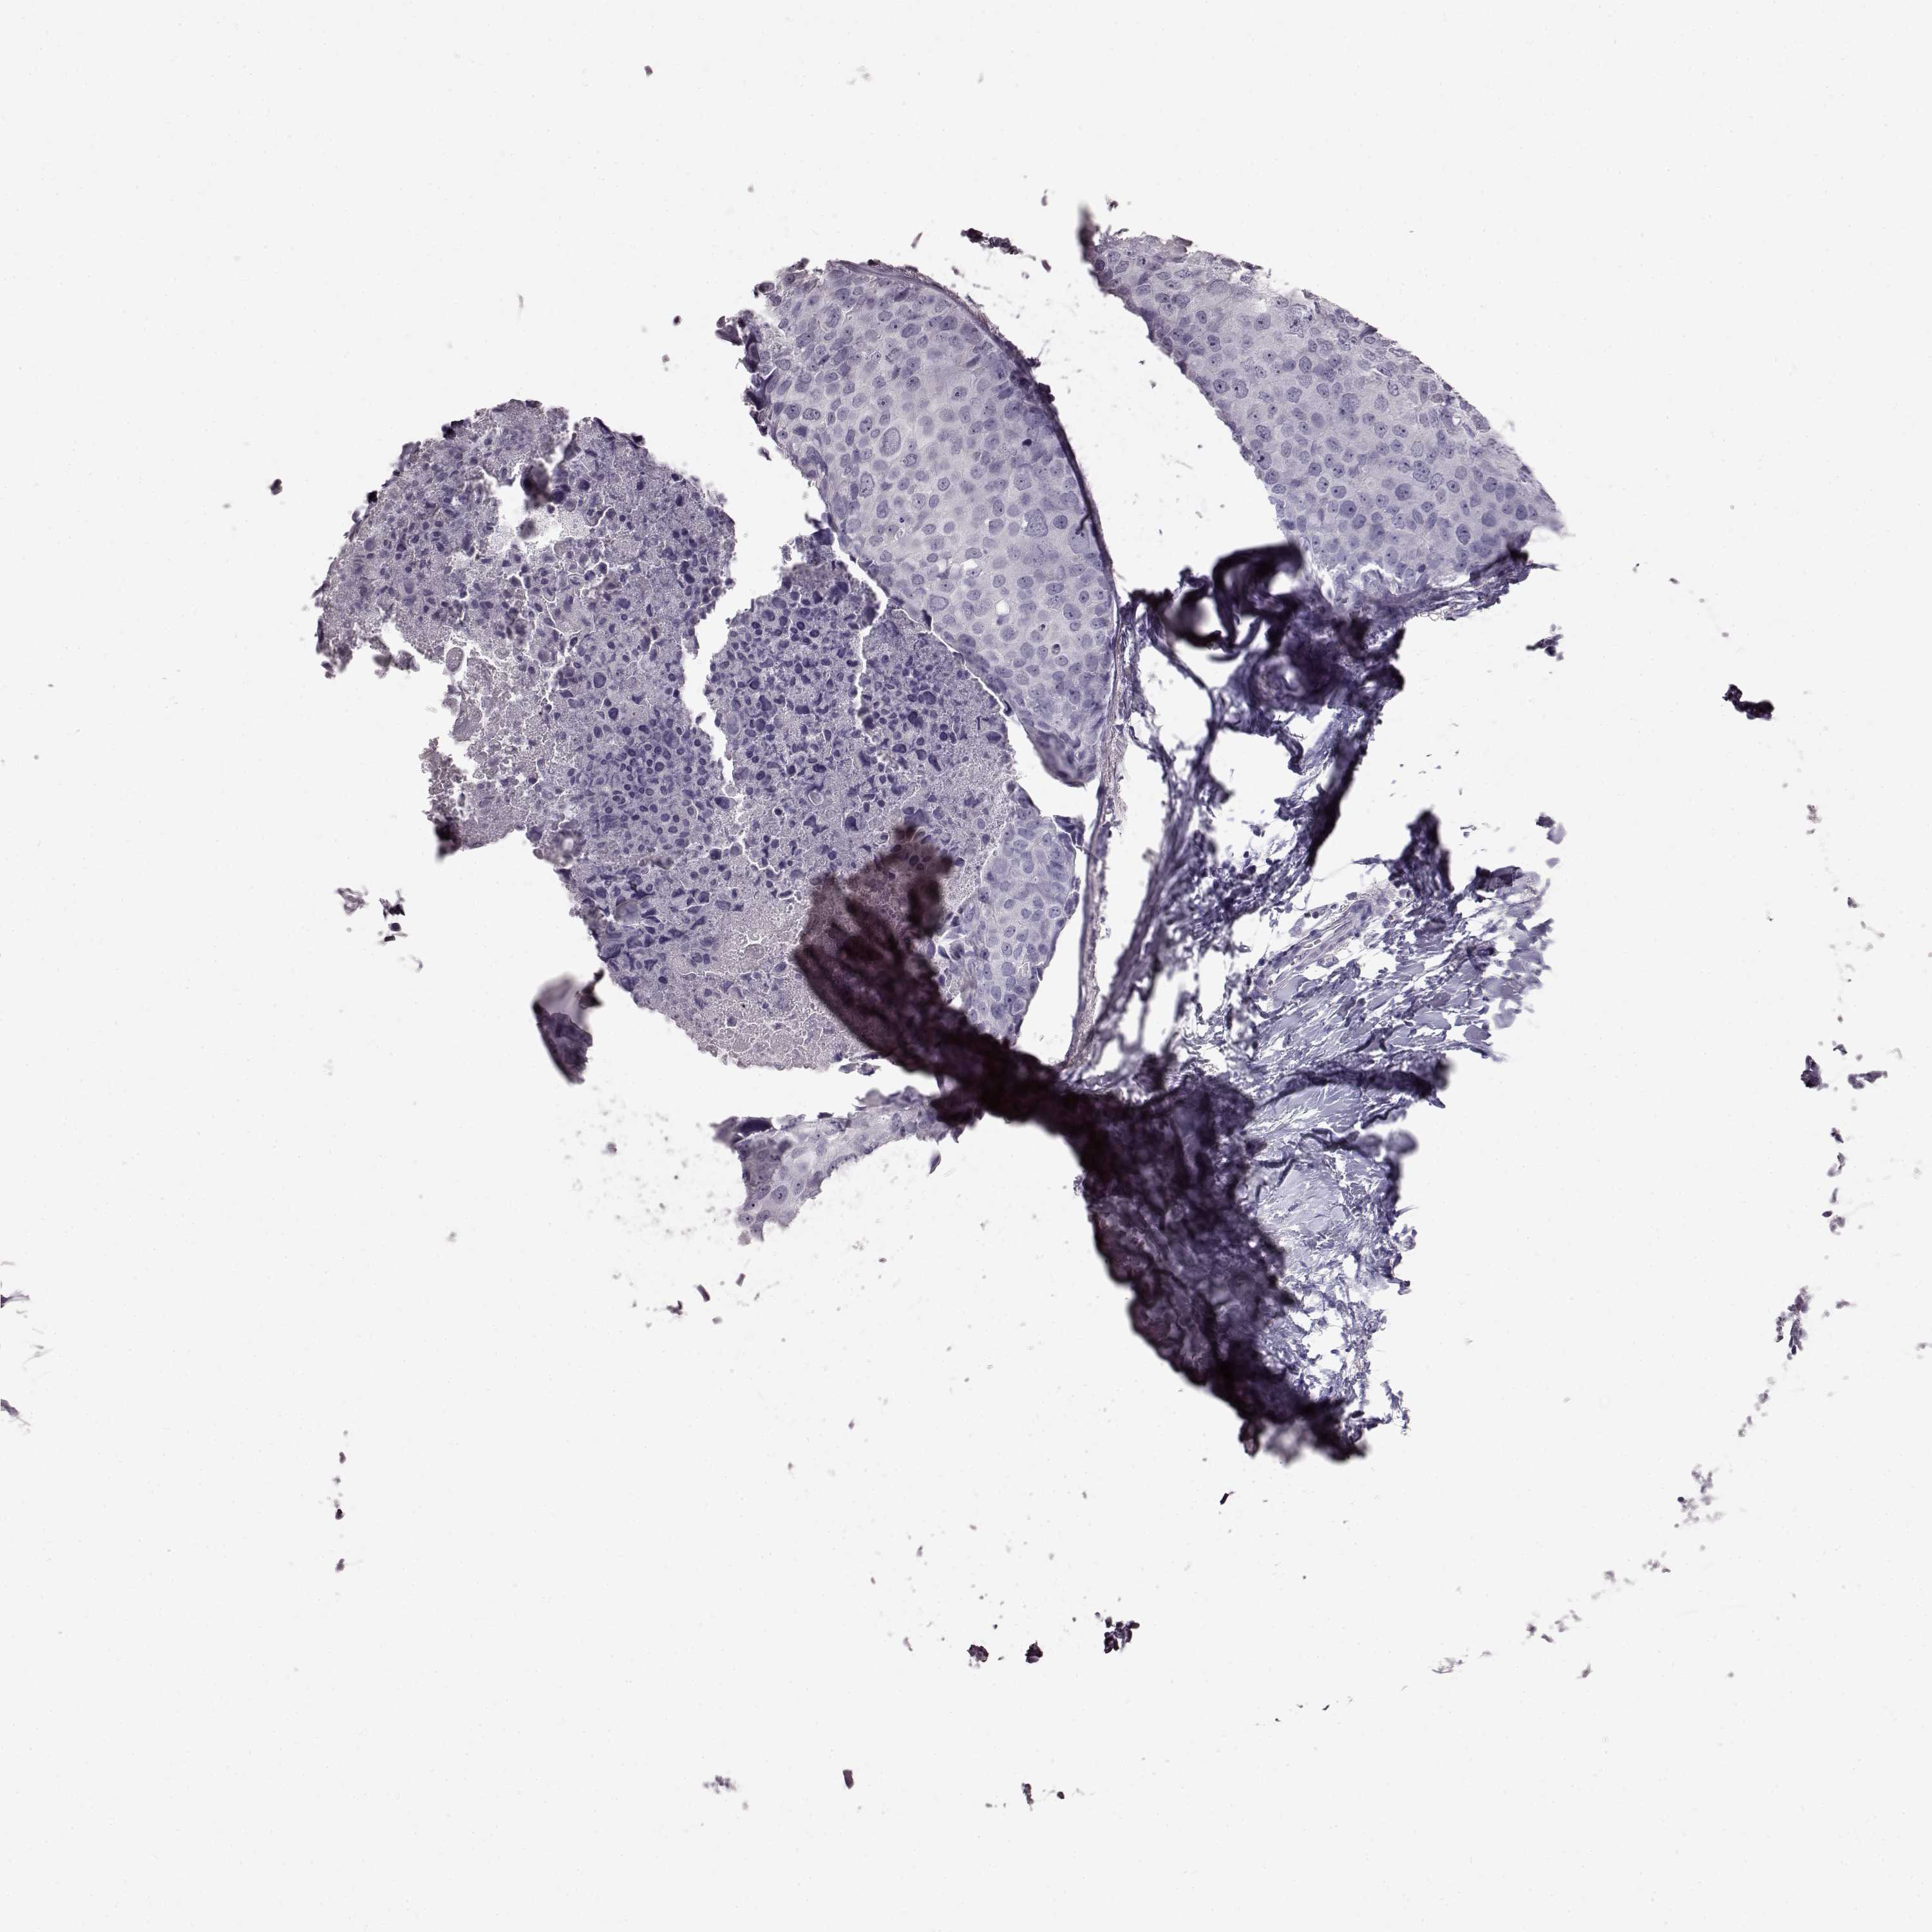

Breast cancer

Human cancer